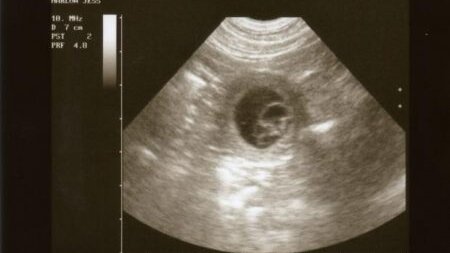

Чаще всего, 4 неделя беременности по акушерским срокам – это очень важный момент в жизни женщины, так как именно в это время большинство будущих мам узнают о своем положении. Не менее важным этот период является и для будущего ребенка, так как плод активно развивается, в это время происходит закладка большинства органов и систем. Рассмотрим, чем еще примечателен срок и какие ощущения могут возникнуть у будущей матери. Итак, наступила четвертая неделя беременности. Это еще очень маленький срок, впереди еще почти восемь месяцев ожидания встречи с малышом...

Четвертая неделя беременности – время, когда «интересное положение» проявляется со всей очевидностью. Организм будущей матери переживает кардинальную гормональную «перестройку», начинается развитие органов плода. Пока еще велика угроза выкидыша, поэтому очень важно контролировать состояние здоровья, при малейших подозрительных симптомах – незамедлительно обращаться к врачу. Что происходит с плодом 4 неделя беременности – время, когда оплодотворенная яйцеклетка превращается в эмбрион. Начинается активное формирование его тканей, органов и систем, происходит «дифференциация» клеток...